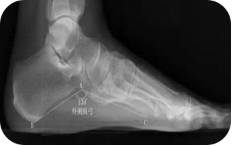

X线测量法:第一跖骨距骨角、距舟覆盖角及跟骨倾斜角等参数的测量,对足进行影像学评估。

足负重前后位、足负重侧位(足内弓角测量、外弓角测量、跟骨倾斜角)。